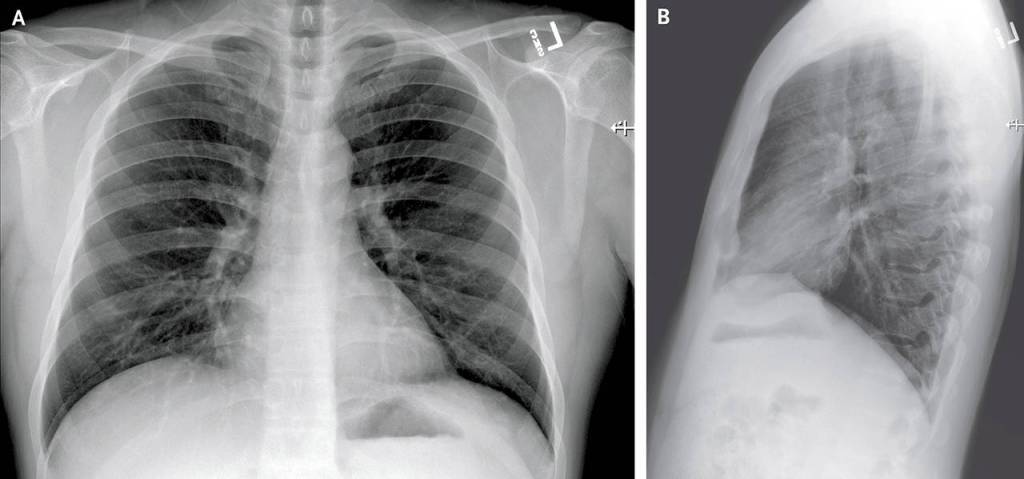

The article details the patient’s symptoms — everything from fatigue, nausea, diarrhea to a runny nose — over time and graphs his lab results. It shows X-rays of his lungs.